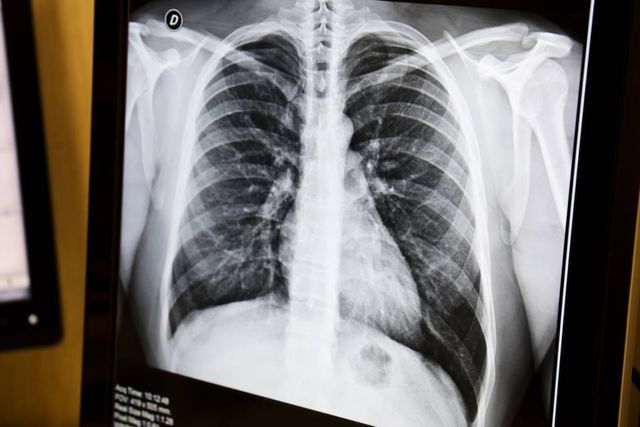

Pochi sintomi di Covid19 o addirittura nessuno Ma la radiografia del torace svela la realtà la malattia si è fatta strada nei polmoni ed è visibile bianco su nero nelle 'lastre' Per la. Rx torace radiografia del torace Per pazienti di età inferiore a 12 anni contattare il CUP al numero 030/ Le pazienti che hanno il dubbio di essere gravide dovrebbero astenersi dall'effettuare esami radiologici. Traducciones en contexto de "radiografia del torace" en italianoespañol de Reverso Context Una radiografia del torace può rivelare un esofago allargato a causa della ulteriore sforzo di cercare di respirare.

La radiografia del torace è un’indagine di rapida esecuzione, non invasiva, che sottopone il paziente ad una dose molto bassa di radiazioni e risulta eseguibile praticamente in ogni paziente e in ogni condizione clinica. L’imaging radiologico non rappresenta un criterio diagnostico per l’infezione da Coronavirus (SarsCov2), ma è in grado di evidenziare l’eventuale polmonite che ad essa si può associare, in tal caso infatti è possibile vedere alla radiografia o alla TC una opacità, definita addensamento. La radiografia del torace offre indicazioni preziose sui grossi vasi (arteria polmonare, aorta ascendente, arco aortico), i polmoni e la trama broncovascolare, la gabbia toracica, il diaframma Si ottengono così indicazioni sull'iperafflusso presente in alcune malattie valvolari, sulla presenza di cogestione polmonare nello scompenso cardiaco.

La radiografia del torace è l’indagine radiografica più frequente ed è sicuramente l’indagine d’elezione nelle patologie toraciche La radiografia utilizza l’esposizione del corpo a basse dosi di radiazioni x per produrre immagini su pellicola degli organi interni Quando le radiazioni penetrano nel corpo vengono assorbite in maniera diversa a seconda delle diverse parti anatomiche. Radiografia del torace le alterazioni radiologiche possono comparire anche prima dei sintomi;. La radiografia del torace è utile, come prima valutazione, nel caso in cui si sospetti una patologia infettiva polmonare (es broncopolmonite) patologia della pleura (es versamento) patologia dell’interstizio (es fibrosi polmonare) patologia cardiaca (es insufficienza cardiaca).